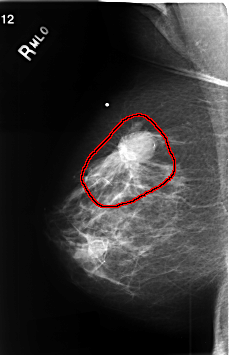

C_0457_1.RIGHT_MLO

FILE: C_0457_1.RIGHT_MLO.OVERLAY

TOTAL_ABNORMALITIES 1

ABNORMALITY 1

LESION_TYPE MASS SHAPE LOBULATED MARGINS SPICULATED

ASSESSMENT 5

SUBTLETY 5

PATHOLOGY MALIGNANT

TOTAL_OUTLINES 1

BOUNDARY